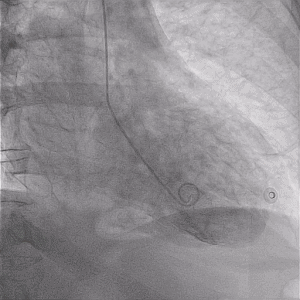

Post MI VSD

60M presenting to peripheral hospital for week of atypical chest discomfort. ECG as follows. Troponin elevated. Transferred to cath lab for ongoing symptoms.